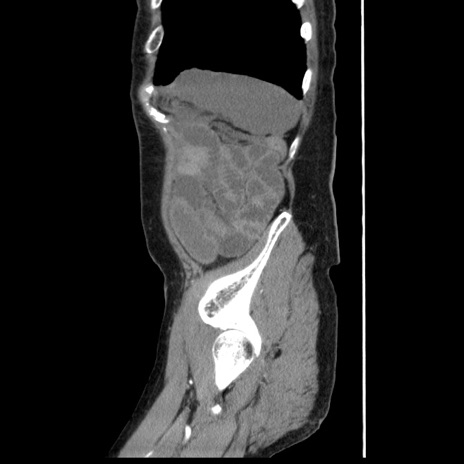

症例1(矢状断像)

【症例】80歳代女性

【主訴】腹痛

【現病歴】8時間前から腹痛あり来院。

【既往歴】糖尿病、脂質異常症、子宮体癌にて子宮全摘術

【身体所見】意識清明・会話良好だが腹痛で苦悶様、全腹部にわたって反跳痛と圧痛あり

【データ】WBC 13600、CRP 0.14、LDH 224、CK 90